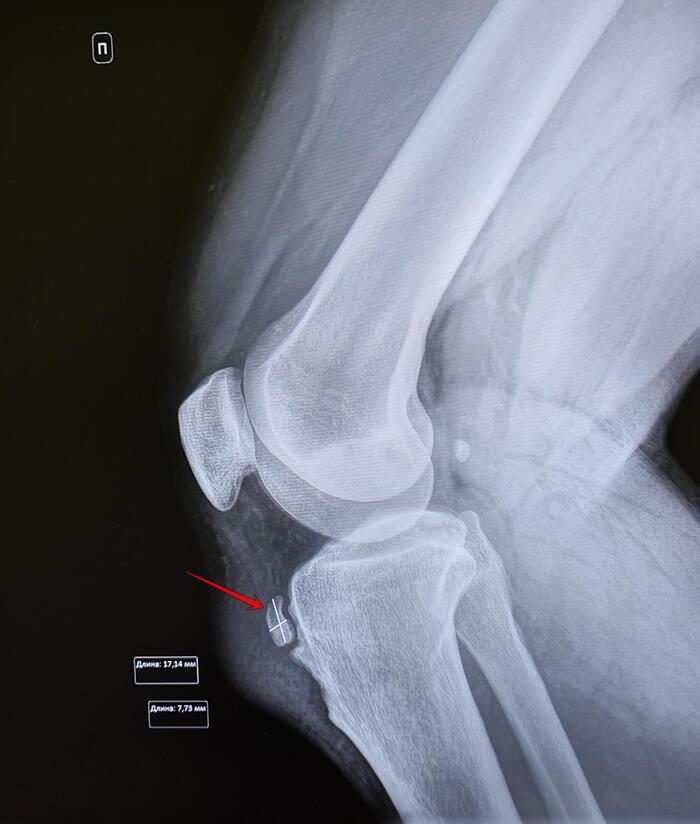

Призывник упал на вытянутую левую руку, обратился за помощью в травмпункт, где был диагностирован закрытый перелом дистального конца диафиза левой локтевой кости со смещением, выполнена закрытая репозиция, наложена гипсовая лонгета, на рентгенологический контроль призывник явился через 2 недели с момента перелома.

При повторном рентгенологическом исследовании выявлено вторичное смещение костного отломка латерально, нарушение оси левой локтевой кости, ее искривление в 17.4 град. Формирующаяся костная мозоль- что по сути означает срастания перелома. Заключение: Неправильно срастающийся перелом дистального конца левой локтевой кости со смещением.